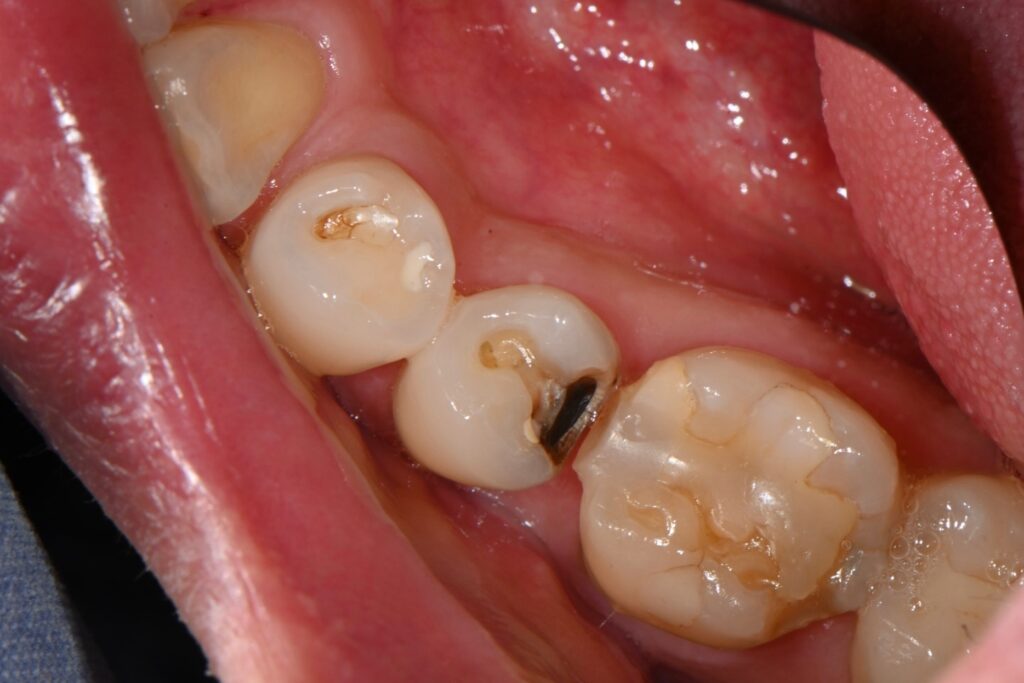

앞서 보여드린 치아를 치료하는 과정입니다

기존의 인레이를 제거하고 나서 충치가 굉장히 깊습니다

이런경우 신경치료의 가능성도 높고

치아삭제가 많은 크라운이나 다른 인레이를 해야 하는데요

하지만 최근 빌드업이라는 치료법으로 치료 하는 과정입니다

역시나 충치가 굉장히 깊습니다

또한 다른 문제가 있습니다

바로 앞에 치아에도 충치가 생겨 있는것이지요

충치균은 세균이기 때문에

그 치아가 충치가 있다면 그 주변에 치아도

같이 충치가 있을 가능성이 높습니다

기존 인레이 하방에 이차우식 제거후

신경치료하지 않고 빌드업 완료 케이스입니다

기존의 골드인레이에 문제가 생겨서 오신분입니다

인레이 하방으로 이차우식이 생긴 경우인데요

대부분 인레이가 오래되거나 음식물이 들어가기 시작하면 생기는 현상입니다

골드인레이를 오년정도 사용하셨고

음식물이 너무 많이 끼여서 뒤쪽에 보면

저렇게 이상한 모양으로 레진필링도 타치과에서 받으셨습니다

그냥 음식물이 끼이니까 급하게 하신것 같은데

오히려 저런부분이 골드인레이 하방에

충치가 생기도록 한 것 같습니다

타치과에서 신경치료 크라운 설명을 들었지만

혹시나 하는 마음으로 내원하신 케이스 입니다.

일단 빌드업으로

최소한의 삭제로 신경치료를 하지 않고

치아를 실려 보도록 하려고 하였습니다

충치를 제거해 나가면서

뒤쪽의 이상한 부분도 깔끔하게 정리하였습니다

그리고 그 부분에 빌드업을 해보도록 합니다,

충치를 제거하고 뒤쪽을 다듬은 모습입니다

정리가 그래도 깔끔하게 된듯한데

불안한 부분은 신경이 가까워서 혹시나

신경치료를 들어갈까 걱정했지만

그래도 적절히 빌드업이 가능했습니다